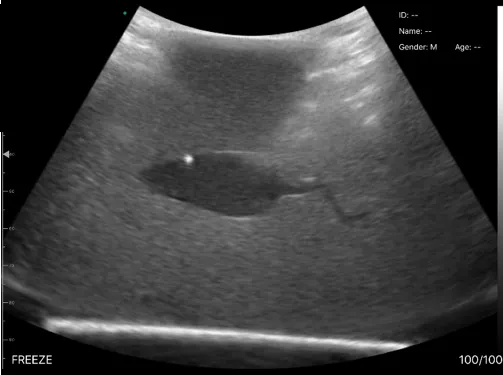

Ultrasound image of the object embedded in gel

The activity entitled ‘Imaging Inside-Out’ involved a hands-on experience where participants used lightweight hand-held ultrasound scanners of varying frequencies to obtain live images of 3D printed miniaturised 3D shapes and mice embedded at different orientations in opaque gels. This activity encouraged a lively and informed discussion between the Scouts and our researchers about medical imaging and the use of animals in research.